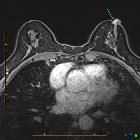

Ultrasound